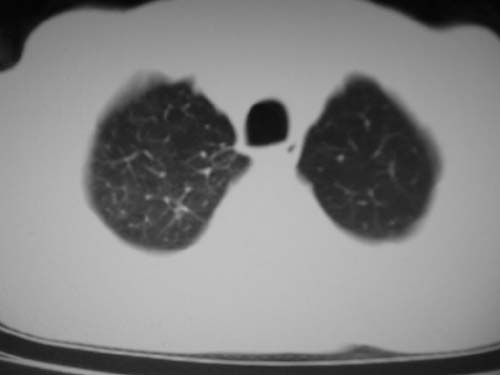

男,80岁

左肺动脉异常增粗,建议增强。

左肺动脉异常增粗,考虑肺动脉狭窄可能。

右肺上叶继发性肺结核。

右侧胸膜增厚、钙化,左侧胸膜反应。

肺动脉段突出,左右肺门不等大,左肺门明显增大,肺动脉干及左肺动脉明显增宽,考虑先天性肺动脉狭窄瓣膜狭窄型。

肺动脉高压,左肺动脉瘤样扩张。